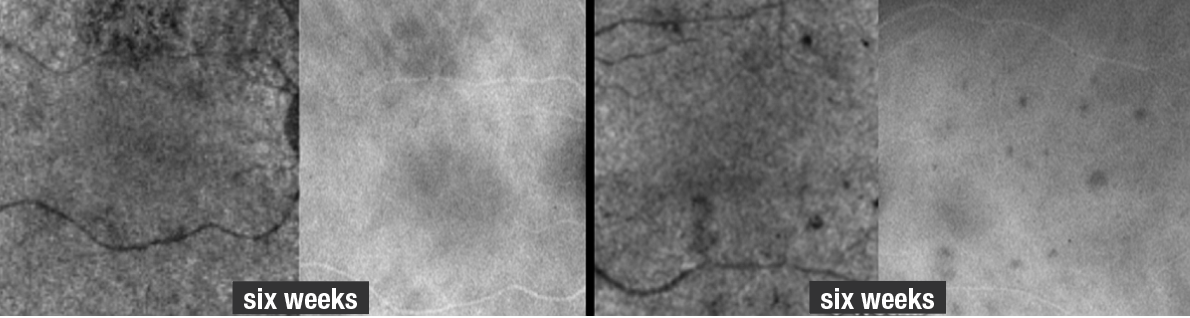

Five weeks after the initial presentation, the patient’s fundus lesions resolved clinically with progressive RPE changes in the right eye only. OCT demonstrated persistent RPE thickening with overlying EZ loss in the right eye superior to the fovea. The remainder of the cube in the right and left eyes demonstrated EZ reconstitution and resolution of ONL hyper-reflectivity with trace ONL thinning. OCTA flow dramatically improved in the left eye, but with a few focal deficits within the macula that correlated to hypofluorescent spots on same-day ICG imaging (Figure 6).

| Figure 6. Optical coherence tomography angiography and indocyanine green angiography of the right and left eyes six weeks after the initial presentation show the lesions had significantly improved but haven’t resolved (compare to Figure 2 for OCTA and ICGA images on initial presentation). A few more spots appear on ICG relative to the OCTA at six weeks, but the extent of improvement can be adequately visualized by both imaging modalities. |

Bottom line

As this case illustrates, multimodal imaging is essential in diagnosing APMPPE and monitoring disease activity. The findings in our patient corroborate what has been previously reported: that is, excellent colocalization of flow voids on OCTA with hypocyanescent changes on ICGA. Additionally, we longitudinally followed the lesions with OCTA, observing resolution of these flow voids. A repeat ICGA and OCTA six weeks after this patient’s initial presentation demonstrated significant improvement of the flow voids, but not complete normalization.

Even several weeks after the symptoms and clinical signs resolved, deficits in choroidal perfusion remained—easily imaged with OCTA and ICGA. Here, OCTA may be a suitable and noninvasive way to image patients with APMPPE and track their disease course over time. RS